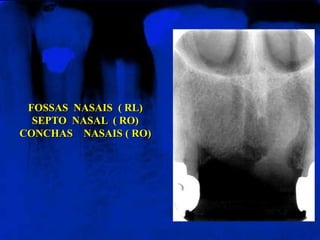

FOSSAS NASAIS ( RL)

SEPTO NASAL ( RO)

CONCHAS NASAIS ( RO)

Apresentam-se nas radiografias

periapicais da região de incisivos

superiores.

Em alguns casos, observam-se, nas

paredes laterias das fossas nasais,

estruturas menos radiolúcidas que

representam as conchas nasais

inferiores (CNI).

FOSSAS NASAIS (RL) SEPTO NASAL ( RO) CONCHAS NASAIS ( RO) Apresentam-se nas radiografias periapicais da região de incisivos superiores. Em alguns casos, observam-se, nas paredes laterias das fossas nasais, estruturas menos radiolúcidas que representam as conchas nasais inferiores (CNI).

FOSSAS NASAIS (RL) SEPTO NASAL ( RO) CONCHAS NASAIS ( RO)